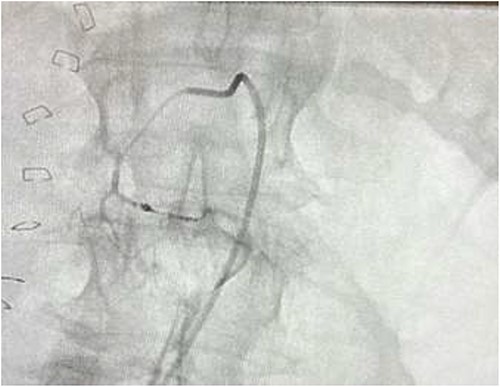

The on-call interventional radiology team performed a successful embolization. A 6-French Sheath was passed through the left common femoral artery, and a 5-French Sim-1 catheter was advanced into the coeliac and common hepatic artery. A 2.4 French Direxon microcatheter was advanced into a branch of the superior mesenteric artery at the site of bleeding. Successful coil embolization with a 2 mm × 2 mm concerto micro coil was performed. A satisfactory angiographic result with DYNA-CT, also known as modern C-arm CT or cone-beam CTA, showed no extravasation.

There were no immediate complications to the procedure. The patient returned to intensive care post-operatively. He remained intubated and vital laboratory tests were stabilized. He experienced acute renal failure post-procedure that required haemodialysis and prolonged intubation (Figs 3 and 4).